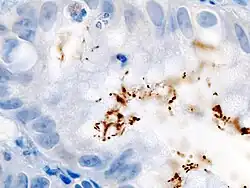

Der direkte Nachweis des H. pylori geschieht durch Probeentnahmen (Biopsien) aus dem unteren Magendrittel und Mikroskopie. Auch kann aus den Proben mittels des Helicobacter-Urease-Test auf das Vorhandensein der Urease geschlossen werden und damit indirekt auf das Vorhandensein des Bakteriums.